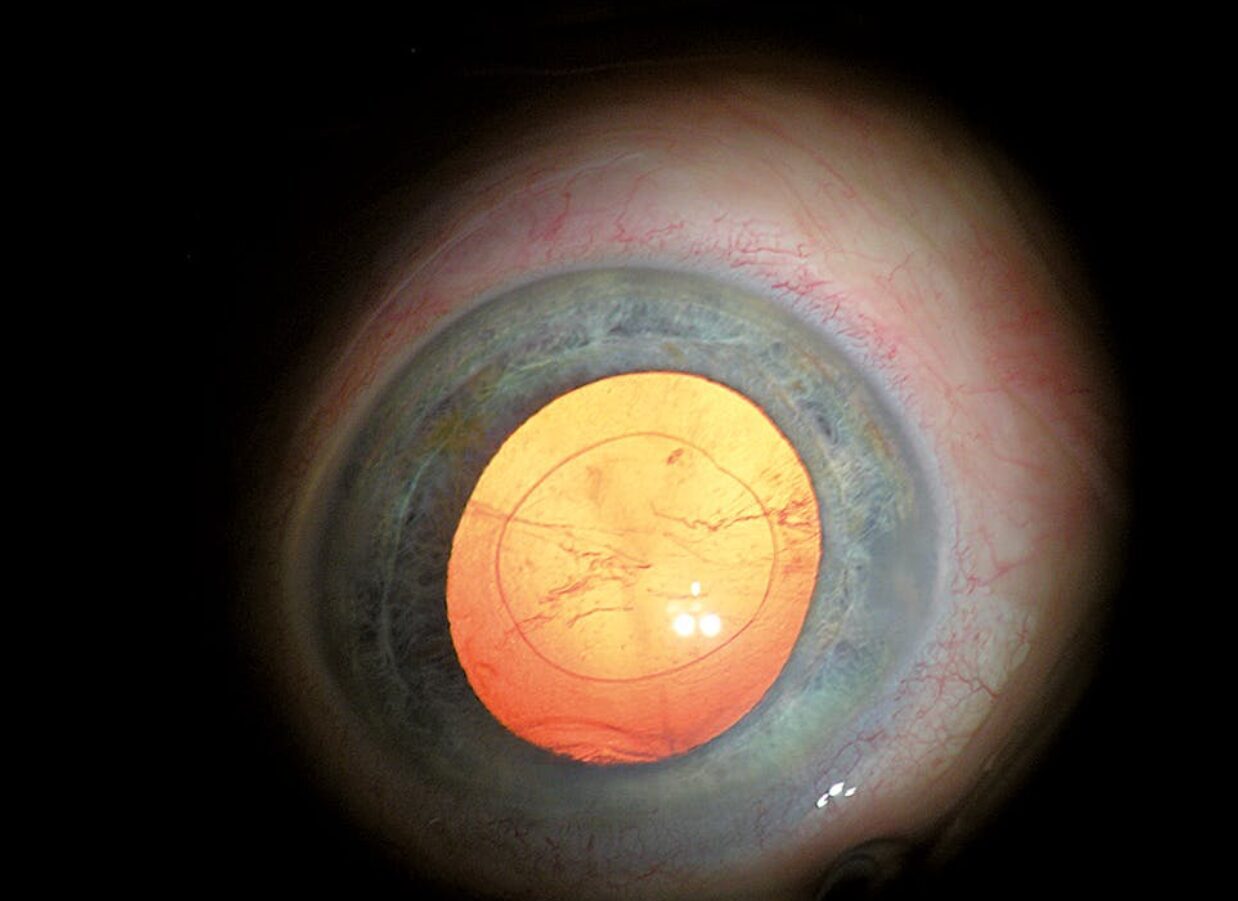

Visualization

With Stereo Coaxial Illumination (SCI), ZEISS OPMI Lumera i incorporates a well established illumination technology for red reflex. Contours are more visible and you can see details of the ocular anatomy that you have never seen before. With this illumination technology, very little light is required to generate the red reflex.